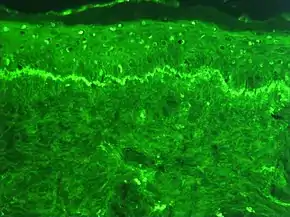

Immunofluorescence is a technique used for light microscopy with a fluorescence microscope and is used primarily on microbiological samples. This technique uses the specificity of antibodies to their antigen to target fluorescent dyes to specific biomolecule targets within a cell, and therefore allows visualization of the distribution of the target molecule through the sample. The specific region an antibody recognizes on an antigen is called an epitope.[1] There have been efforts in epitope mapping since many antibodies can bind the same epitope and levels of binding between antibodies that recognize the same epitope can vary.[2] Additionally, the binding of the fluorophore to the antibody itself cannot interfere with the immunological specificity of the antibody or the binding capacity of its antigen.[3] Immunofluorescence is a widely used example of immunostaining (using antibodies to stain proteins) and is a specific example of immunohistochemistry (the use of the antibody-antigen relationship in tissues). This technique primarily makes use of fluorophores to visualise the location of the antibodies.[4]

Immunofluorescence can be used on tissue sections, cultured cell lines, or individual cells, and may be used to analyze the distribution of proteins, glycans, and small biological and non-biological molecules. This technique can even be used to visualize structures such as intermediate-sized filaments.[5] If the topology of a cell membrane has yet to be determined, epitope insertion into proteins can be used in conjunction with immunofluorescence to determine structures.[6] Immunofluorescence can also be used as a "semi-quantitative" method to gain insight into the levels and localization patterns of DNA methylation since it is a more time-consuming method than true quantitative methods and there is some subjectivity in the analysis of the levels of methylation.[7] Immunofluorescence can be used in combination with other, non-antibody methods of fluorescent staining, for example, use of DAPI to label DNA. Several microscope designs can be used for analysis of immunofluorescence samples; the simplest is the epifluorescence microscope, and the confocal microscope is also widely used. Various super-resolution microscope designs that are capable of much higher resolution can also be used.[8]